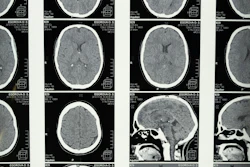

The prototype MRI scanner identified most key pathologies in all 25 patients, compared with the conventional 3-tesla scanner: In one brain tumor case, both the 0.055-tesla and conventional MRI images showed a mass in the right parietal cortex that was "hypointense in T1W and hyperintense in T2W," the group wrote. The study also demonstrated the following:

- T1W images on both types of MRI scanners showed clear asymmetry between the right and left hemisphere, indicating a cystic lesion.

- The prototype scanner showed "excellent sensitivity and correspondence" with the conventional scanner in identifying a choroid plexus cyst at the occipital horn of the right lateral ventricle.

- Both types of scanners identified hematoma on a subacute intracranial hemorrhage case.

- The 0.055-tesla scanner showed "little susceptibility" to artifacts from metallic clips and stents compared to the high-field device.